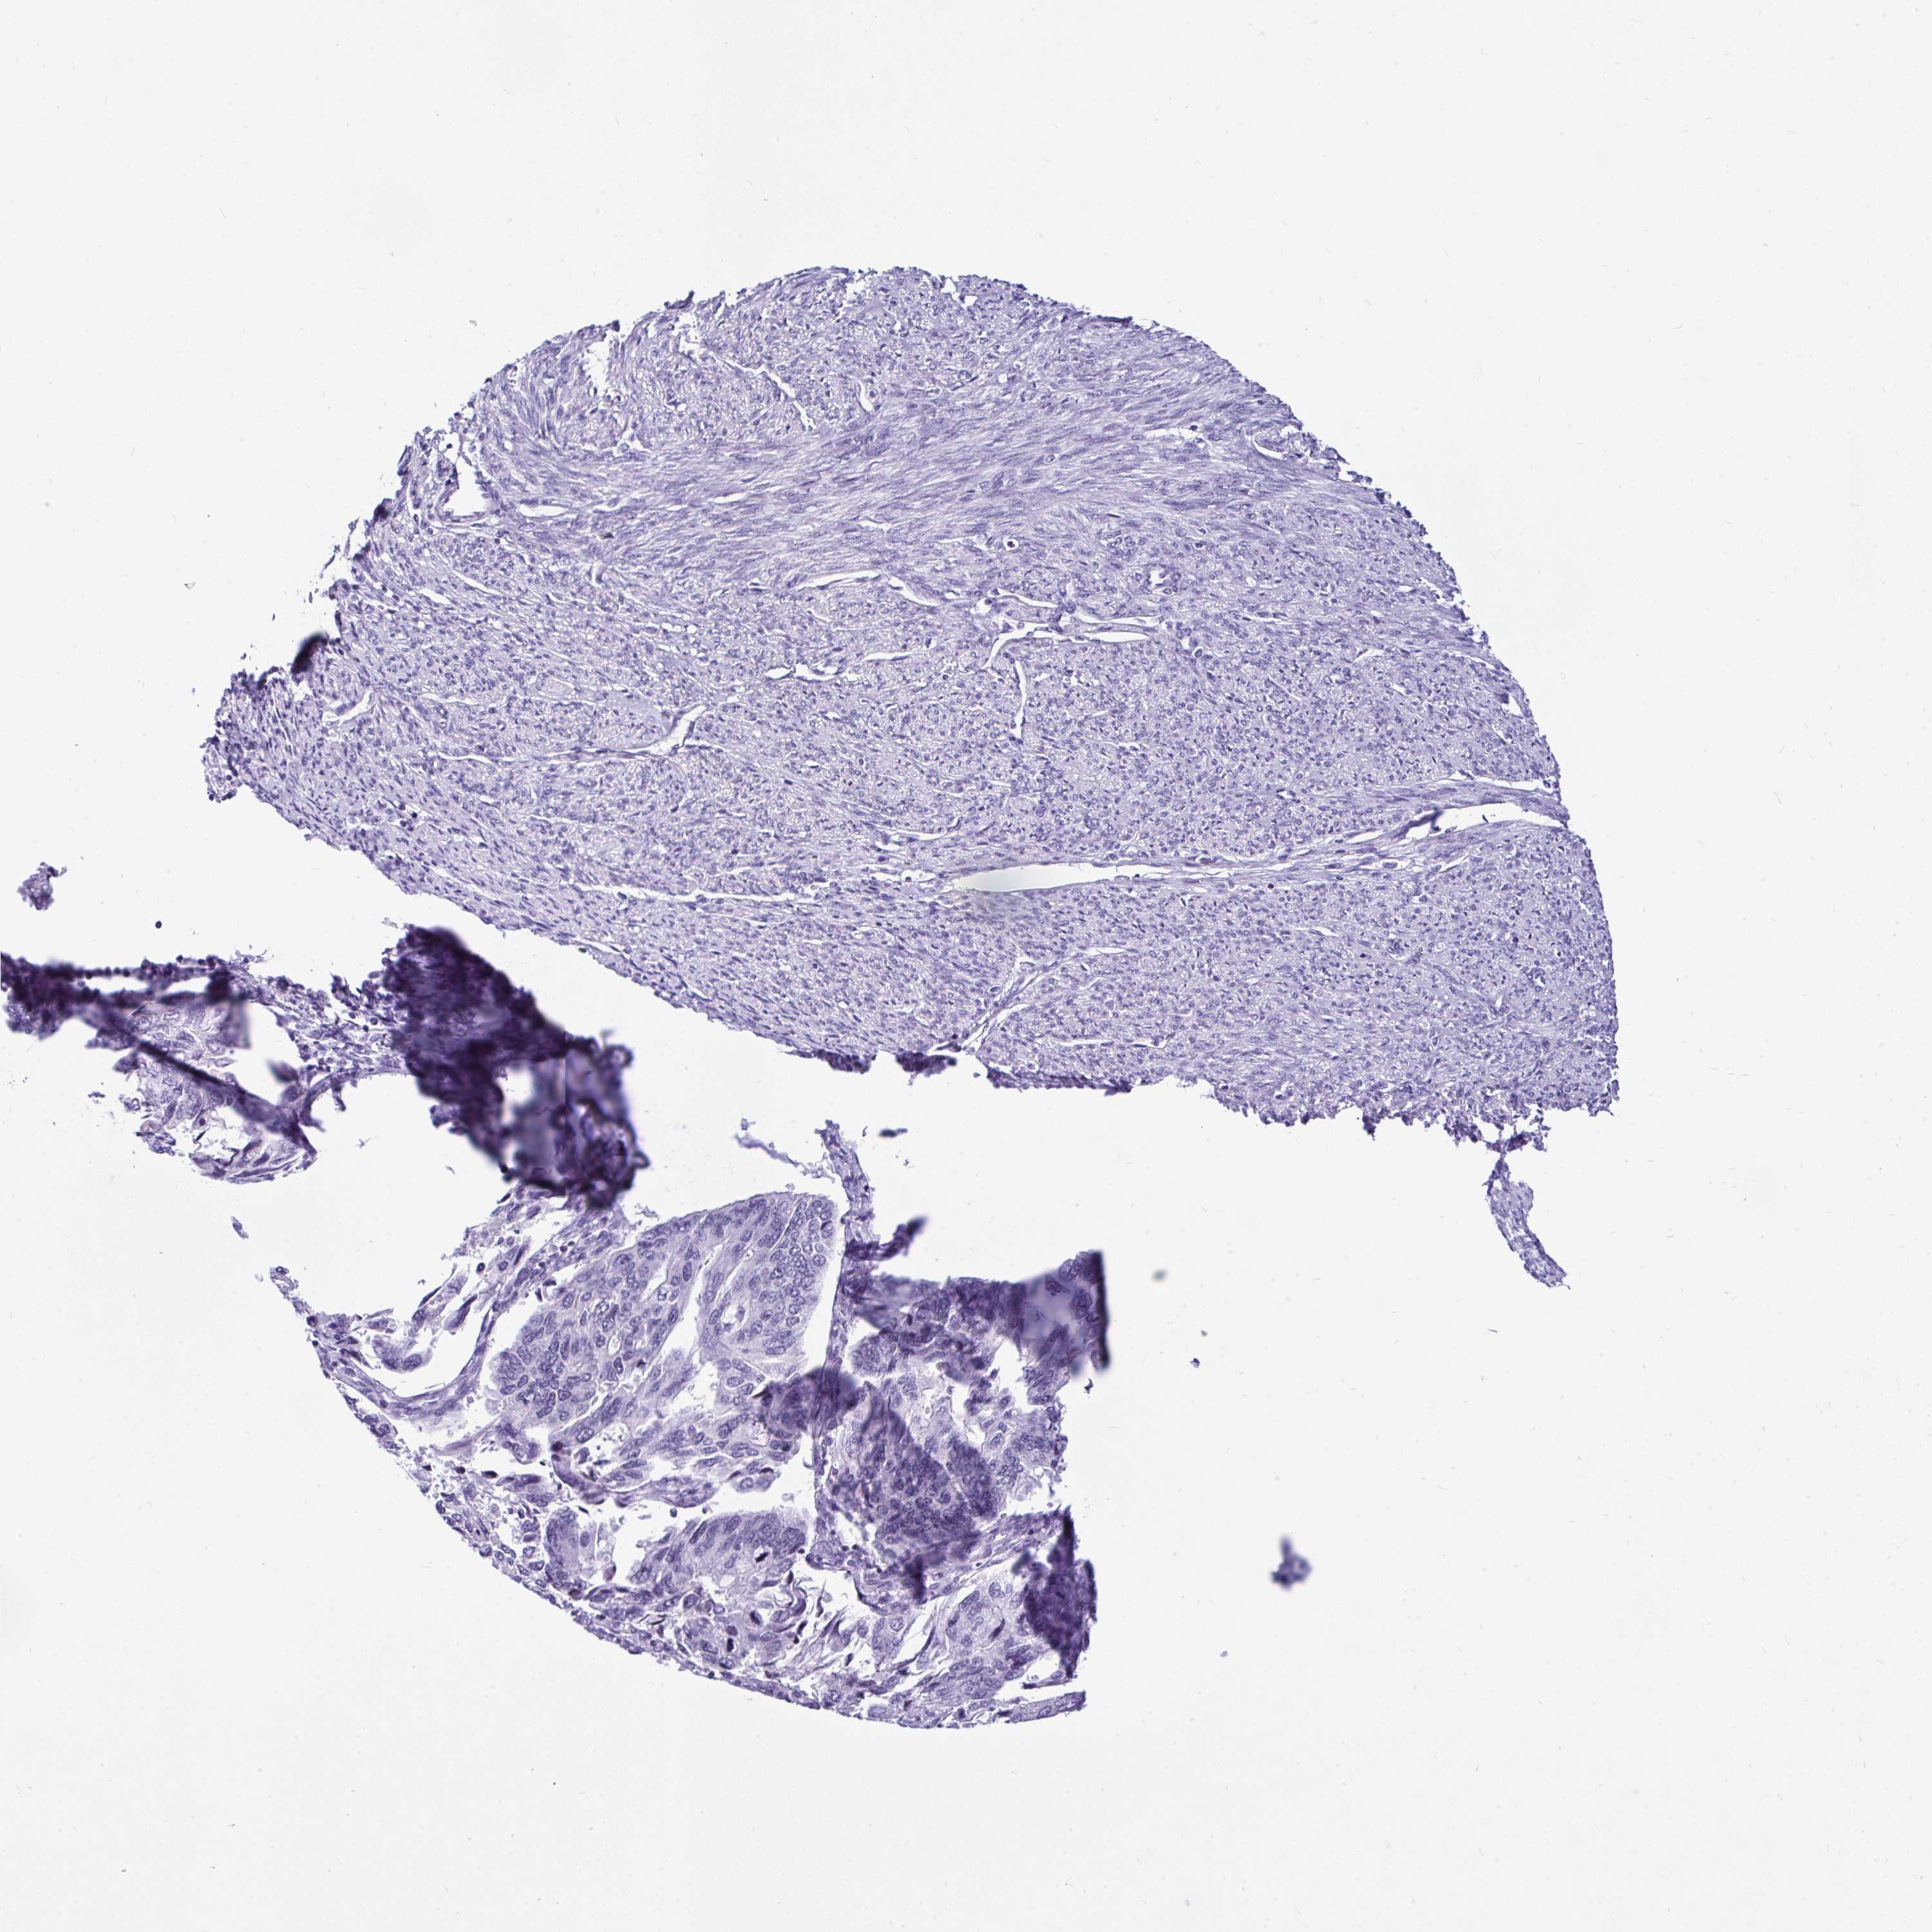

ENDOMETRIAL CANCER - Protein expressioni

A mouse-over function shows sample information and annotation data. Click on an image to view it in a full screen mode. Samples can be filtered based on level of antibody staining by selecting one or several of the following categories: high, medium, low and not detected. The assay and annotation is described here.

Note that samples used for immunohistochemistry by the Human Protein Atlas do not correspond to samples in the TCGA dataset.

Antibody stainingi

Antibody staining in the annotated cell types in the current human tissue is reported as not detected, low, medium, or high, based on conventional immunohistochemistry profiling in selected tissues. This score is based on the combination of the staining intensity and fraction of stained cells.

Each image is clickable and will lead to virtual microscopy that enables deeper exploration of all samples and also displays staining intensity scores, fraction scores and subcellular localization as well as patient and tissue information for each sample.

Antibody HPA055114

Staining

High

Medium

Low

Not detected

Intensity

Strong

Moderate

Weak

Negative

Quantity

>75%

75%-25%

<25%

None

Location

Nuclear

Cytoplasmic/membranous

Cytoplasmic/membranous,nuclear

Adenocarcinoma, NOS

Carcinoma, NOS

Adenocarcinoma, metastatic, NOS